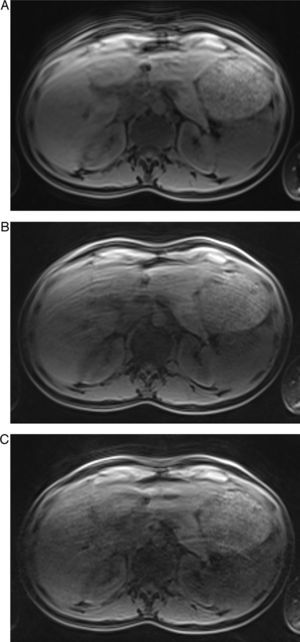

Las adquisiciones con FR=2 y FR=4 en apnea presentaron una calidad de imagen diagnóstica intermedia principalmente a causa de los valores más altos de artefactos por granulado de los píxeles (p=0,006), aunque se obtuvieron significativamente mejores resultados con un FR=2 (p=0,004). En general, el FR=6 no tuvo calidad de imagen diagnóstica (fig. 1), con diferencias significativas con respecto a un FR=4 (p=0,01) y a un FR=2 (p=0,004). El granulado de los píxeles fue la causa principal de esta calidad de imagen no diagnóstica para el FR=6 en comparación con un FR=4 (p=0,004) y FR=2 (p=0,004). Además, el FR=6 tuvo una tasa de artefactos de aliasing más baja, pero casi diagnóstica (3,7±0,6).

Imágenes en 3D EG potenciadas en T1 obtenidas en apnea con FR=2 (A), FR=4 (B) y FR=6 (C) del mismo individuo. Obsérvese el empeoramiento de la calidad de imagen al aumentar el FR. La calidad de imagen de (A) se consideró excelente, con casi ningún artefacto. Obsérvese la clara definición del margen del hígado, páncreas y bazo y del contorno de las ramas de la vena porta. En (B y C) hay un empeoramiento progresivo de los artefactos, sobre todo del granulado de los píxeles y aliasing en el centro de la imagen. Aunque solo aparece una ligera borrosidad de las estructuras hepaticas en FR=4 (B), los artefactos que aparecen en la imagen (C) provocan una borrosidad importante y menor definición del hígado que hacen que (C) sea no diagnóstica.